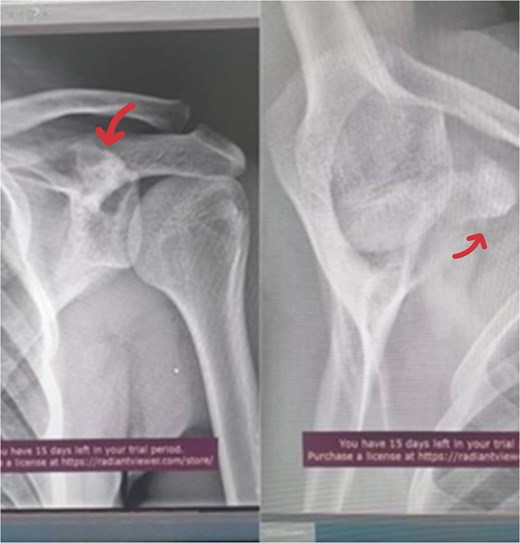

A 17-year-old male presented with left shoulder pain and limited range of motion for 2 months, with no history of trauma or prior medical or surgical issues. On examination, there was tenderness localized to the coracoid process. Initial laboratory tests, including complete blood count (CBC), C-reactive protein (CRP), and erythrocyte sedimentation rate (ESR), all normal. Conservative management with rest and non-steroidal anti-inflammatory drugs (NSAIDs) was initiated, but there's no improvement. Initially, imaging with an X-ray revealed a suspicious lesion at the base of the coracoid process (Fig. 1), prompting further evaluation with magnetic resonance imaging (MRI) without contrast, which confirmed the lesion in the base of the coracoid with surrounding fluid and edema extending to the coracoid-humeral space (Fig. 2).

MRI without contrast of the left shoulder show a cortical and subcortical bony defect at the glenoid basecoracoid junction with hyperintense lesion measuring 8 × 7 mm (indicated by arrow), also intense bone marrow edema at the coracoid processes and the glenoid base-coracoid with surrounding fluid and edema extending to the coracoid-humeral space was seen.